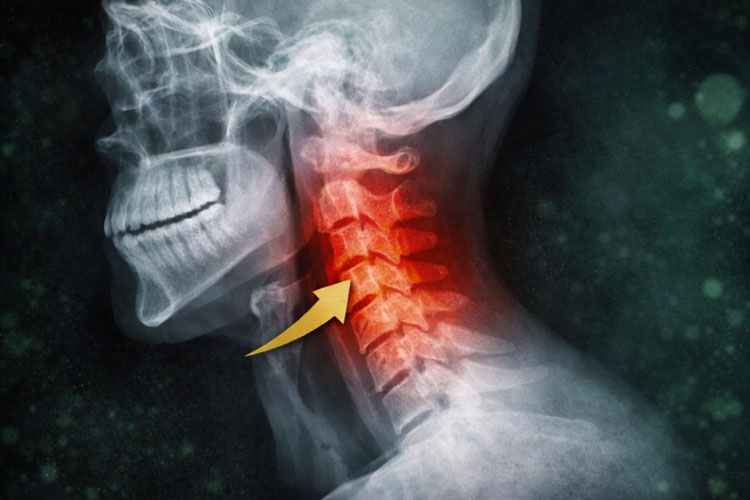

Quando você inclina a cabeça para olhar o celular, o que realmente está acontecendo não é apenas uma “má postura”. Do ponto de vista biomecânico, você está deslocando o centro de gravidade da cabeça para frente, aumentando drasticamente a carga sobre a coluna cervical.

A cabeça humana pesa, em média, entre 4,5 e 5,5 kg em posição neutra. No entanto, a cada 15 graus de inclinação para frente, o peso efetivo que a coluna precisa sustentar aumenta exponencialmente. Em inclinações comuns no uso do celular, 45 a 60 graus, essa carga pode ultrapassar 20 kg.

Ou seja: sua coluna cervical passa a sustentar o equivalente a uma criança pequena apoiada continuamente sobre ela.

A coluna cervical foi projetada para manter uma curvatura natural chamada lordose cervical. Essa curva distribui forças, absorve impacto e protege discos, articulações e nervos.

- A lordose cervical se retifica ou se inverte

- Os discos intervertebrais sofrem compressão desigual

- Os músculos posteriores entram em sobrecarga crônica

- Os ligamentos se alongam além do limite fisiológico

- As articulações facetárias passam a sofrer microtraumas repetidos